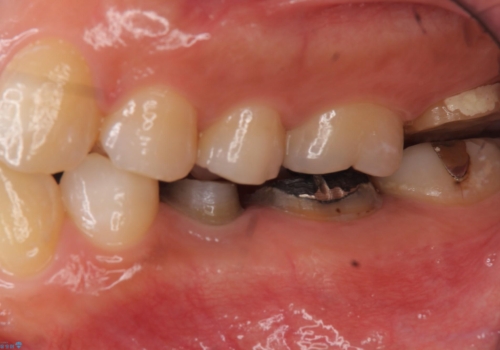

高さがないため、歯肉と歯槽骨の手術(歯周外科手術)APFを行ってから、最終的な被せ物にしました。

今回は歯周外科処置を行い、歯の周りの歯肉の高さをさげるようにしました。

骨からしっかり処置をしないと、歯肉は容易に増殖します。